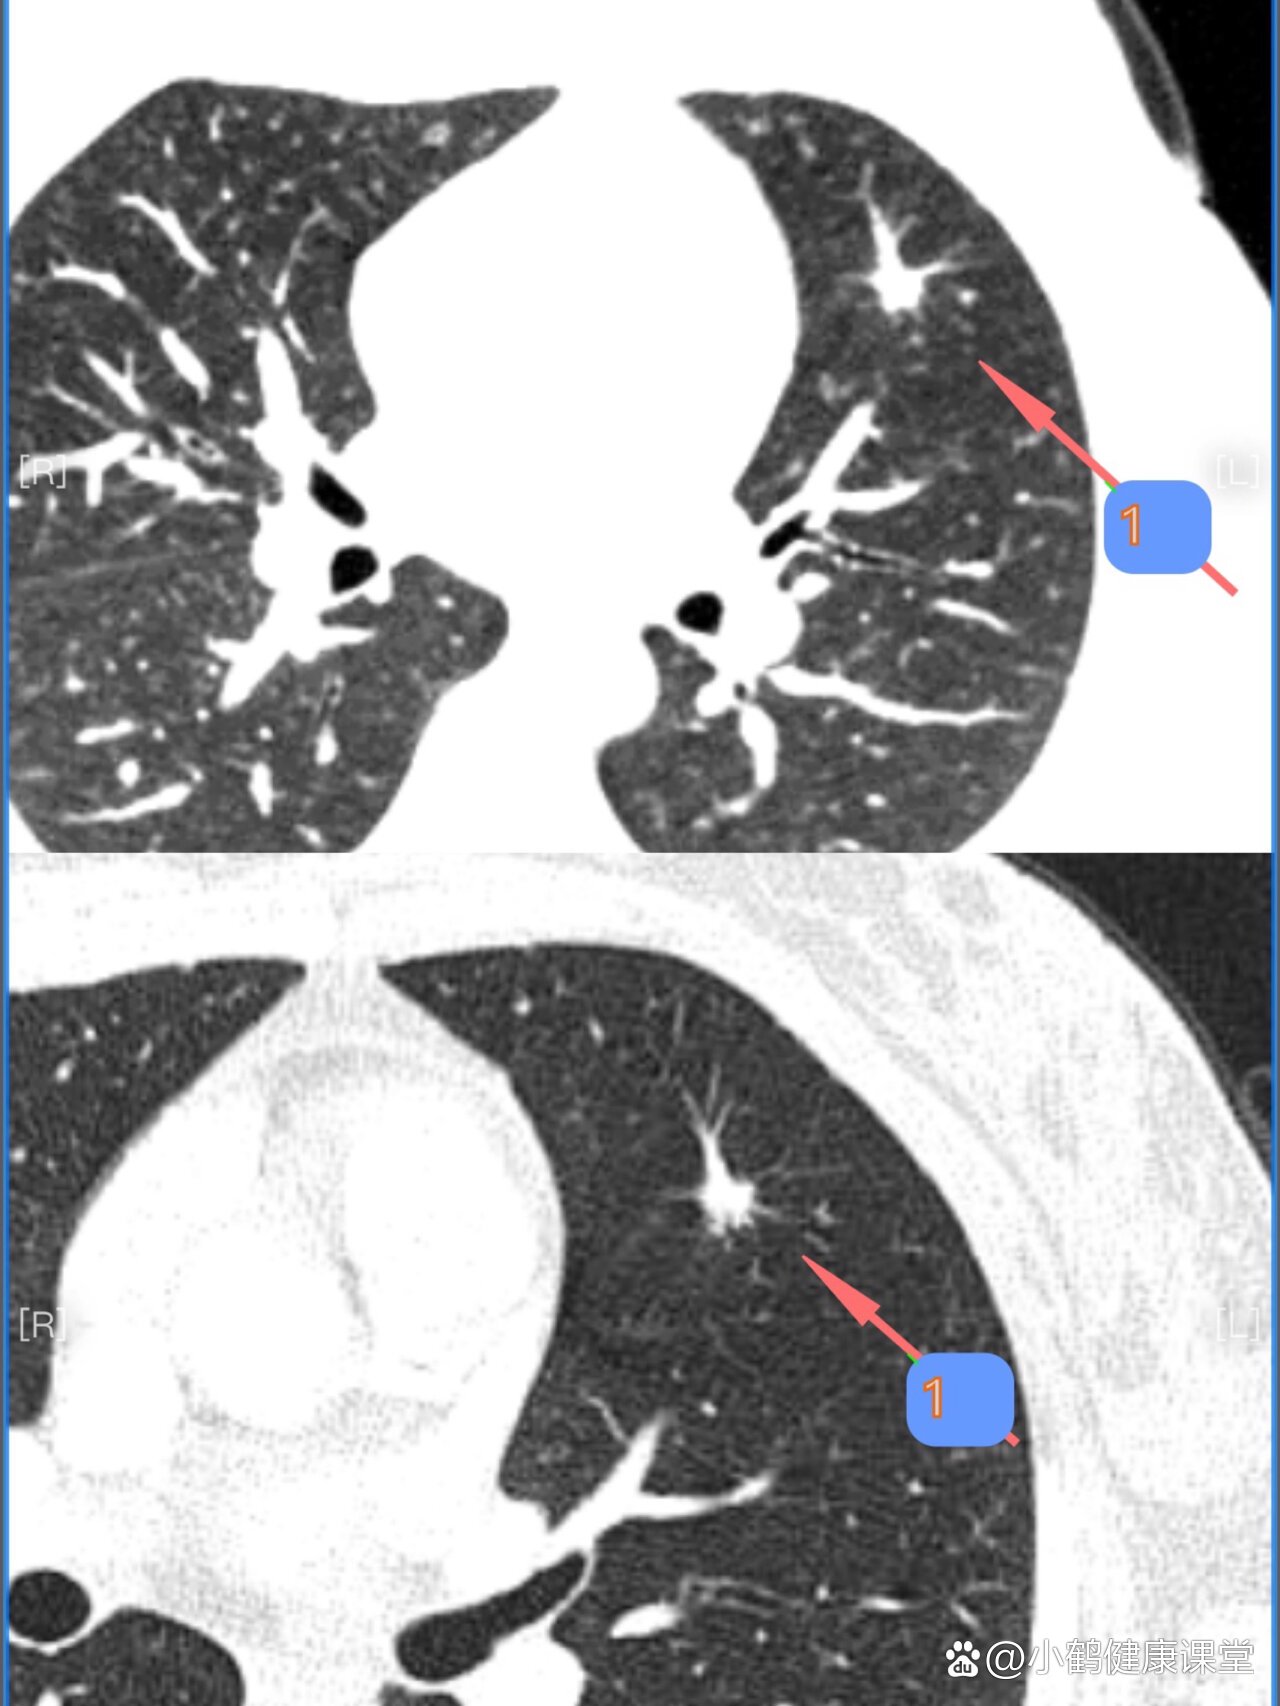

警惕肺癌看图认识肺结节恶性特征之毛刺征

图片尺寸818x1000